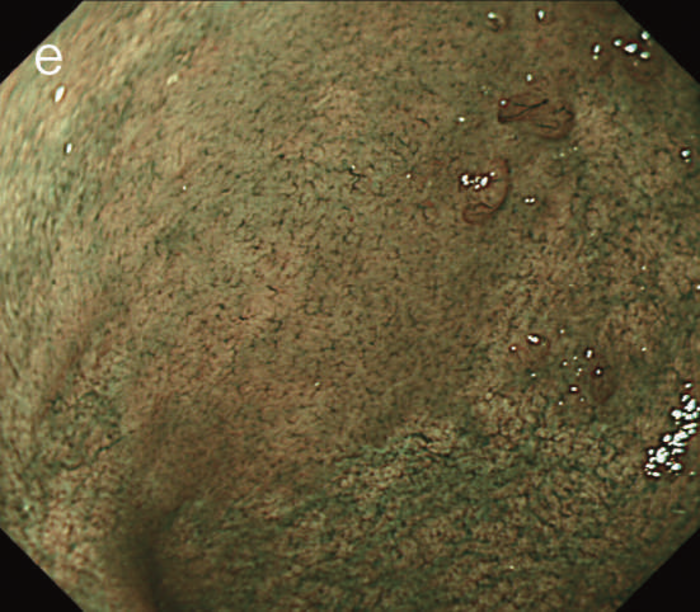

- 白色光像:直腸(直腸S状部)の発赤調変化。背景粘膜は寛解期にあった。

- 色素内視鏡像:病変辺縁が明瞭となるが,病変肛門側で不明瞭であった。

- NBI拡大像:口径不同,不均一な微小血管と不整な表面構造所見を認めた。

- pit pattern像:小型の類円形,管状pitを認めた。